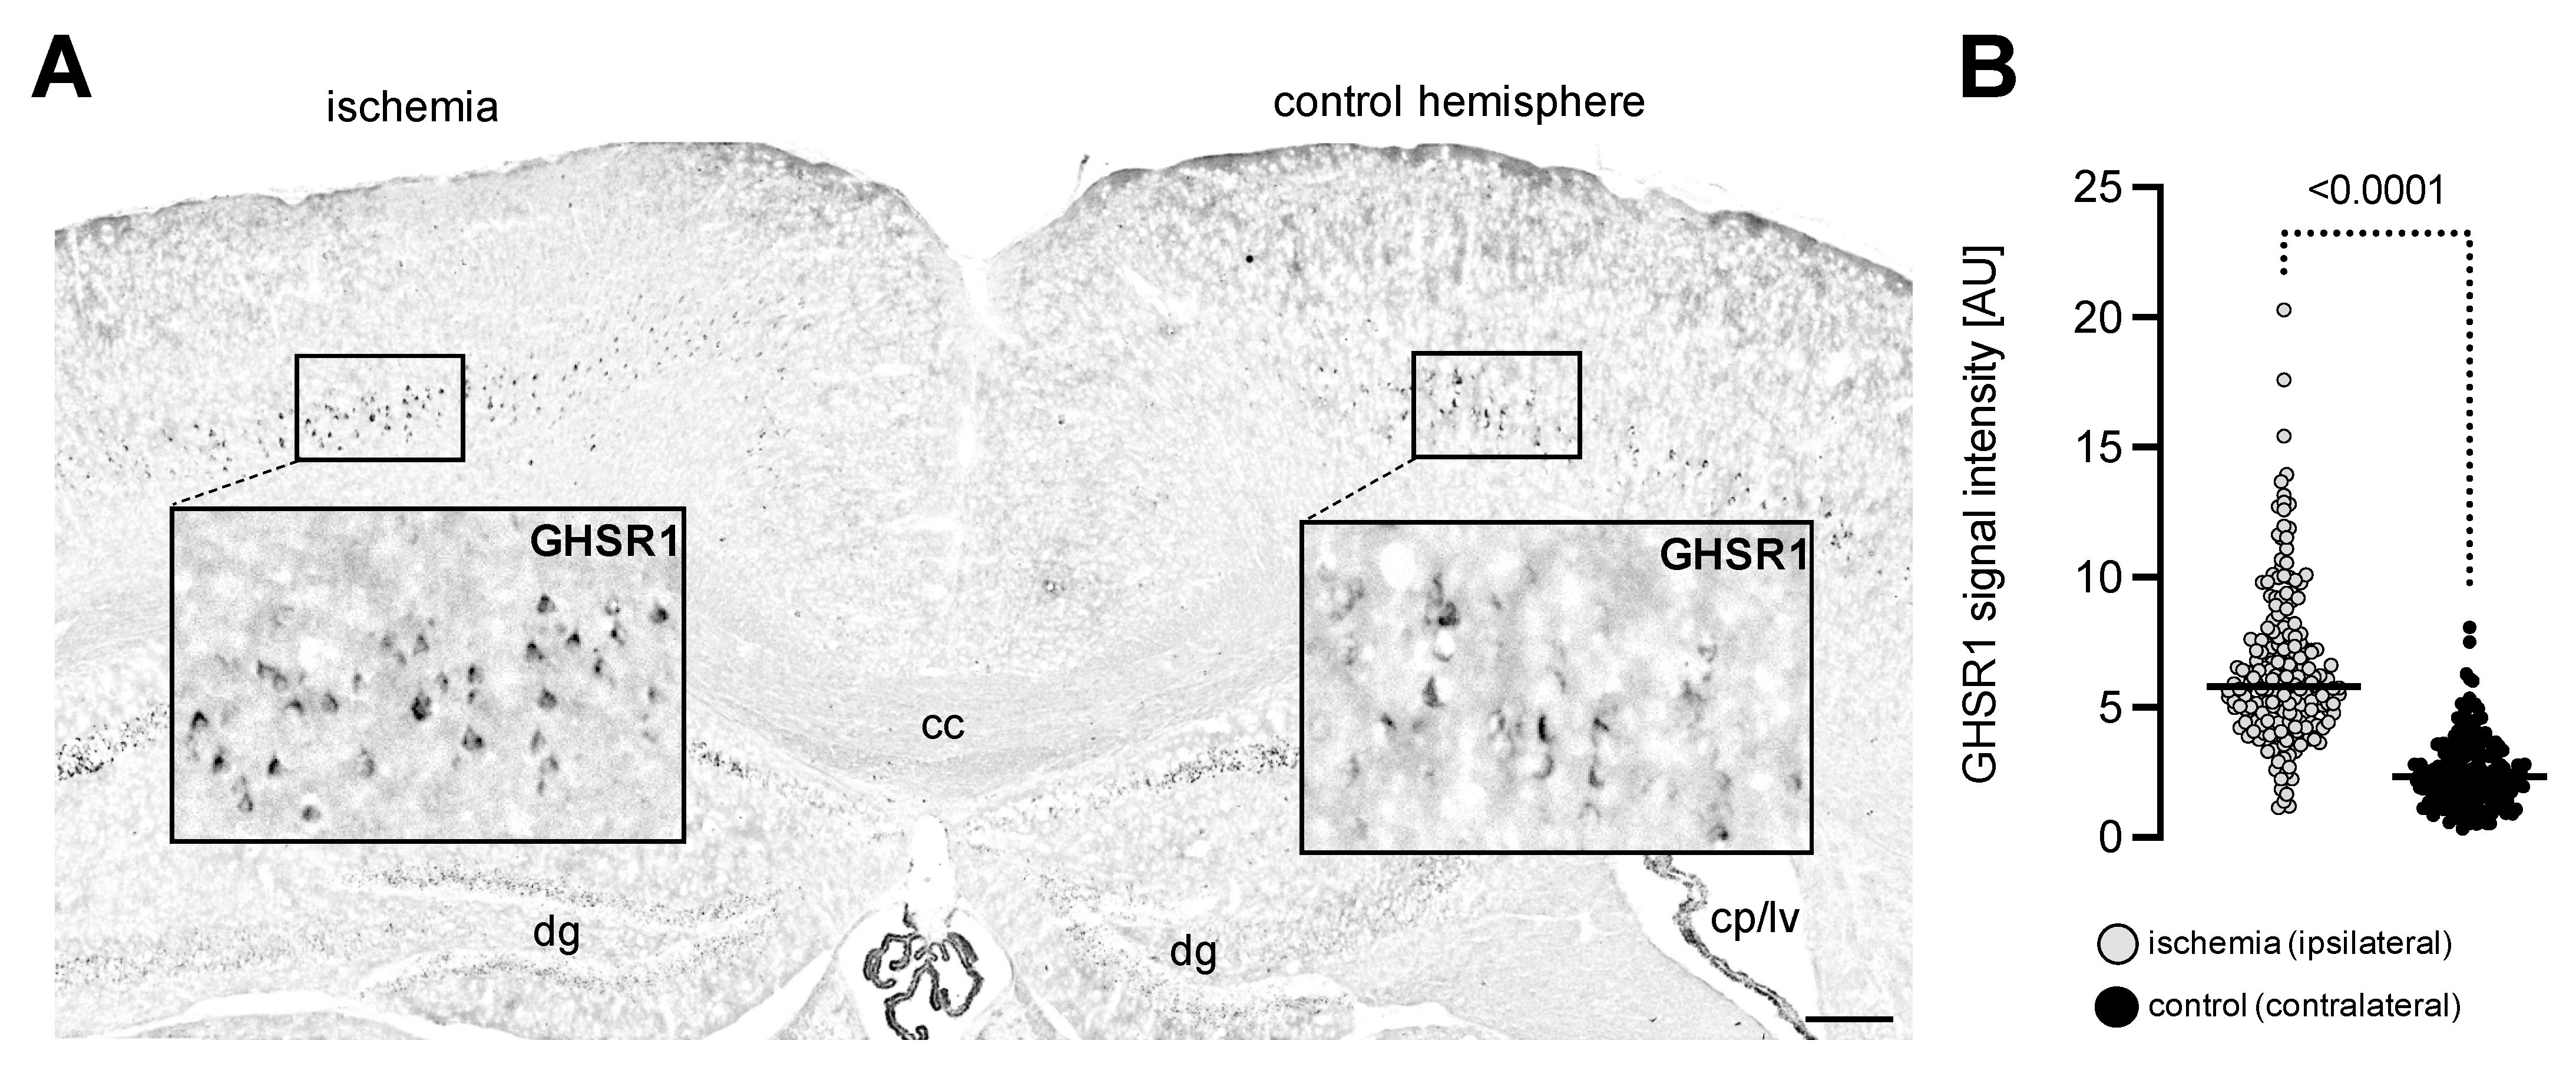

3.1. Experimental Ischemia In Vivo Leads to Increased GHSR1 Expression Levels in Cerebral Cortex Cells